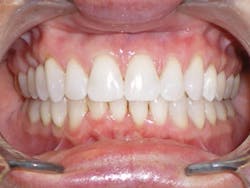

Four weeks later, Evin began his clear aligner treatment (see Figure 1). He was seen for follow-up clear aligner visits at six-week intervals until his treatment was completed. During his clear aligner treatment, Evin maintained three-month recalls with the hygienist. His home care was excellent, in part due to the benefit of aligners being removable.

The six-week follow-up visits with Evin were eye-opening! I had the opportunity to observe his periodontal condition improve at each interval. After 30 aligners, or 15 short months, Evin's clear aligner orthodontic treatment was completed and final photos were taken. His bite was checked to confirm we had achieved our initial goal. Evin now had the appropriate overbite, overjet, and class I occlusion with proper posterior intercuspation with no interferences.

Figure 1

His healthy occlusion was reflected in his gum tissue. Evin finished with nearly a full resolution of his periodontal deterioration. What was originally swollen, inflamed, and bleeding gum tissue that had lost most of its gingival architecture was now very healthy and had regained all components of normal gingival architecture. His gingival tissue was now stippled, clean, pink, tight, and displayed the shallow pocketing of 1-3 mm with no bleeding (compared to his 4-5 mm initial probings). The gingival tissue on the buccal of No. 23 resolved to the level where no further periodontal intervention was recommended. The gingival tissue from teeth Nos. 22-27 had never been touched by a scalpel, laser, or any other periodontal procedure other than the original scaling and root planing, followed by clear aligner therapy.

Evin is a perfect example of this. He always had beautiful teeth. Dr. Miraglia could see that they were just in the wrong place! Insufficient space, as a result of improper arch forms is the cause of crowding, not "crooked" teeth (see Figure 1).